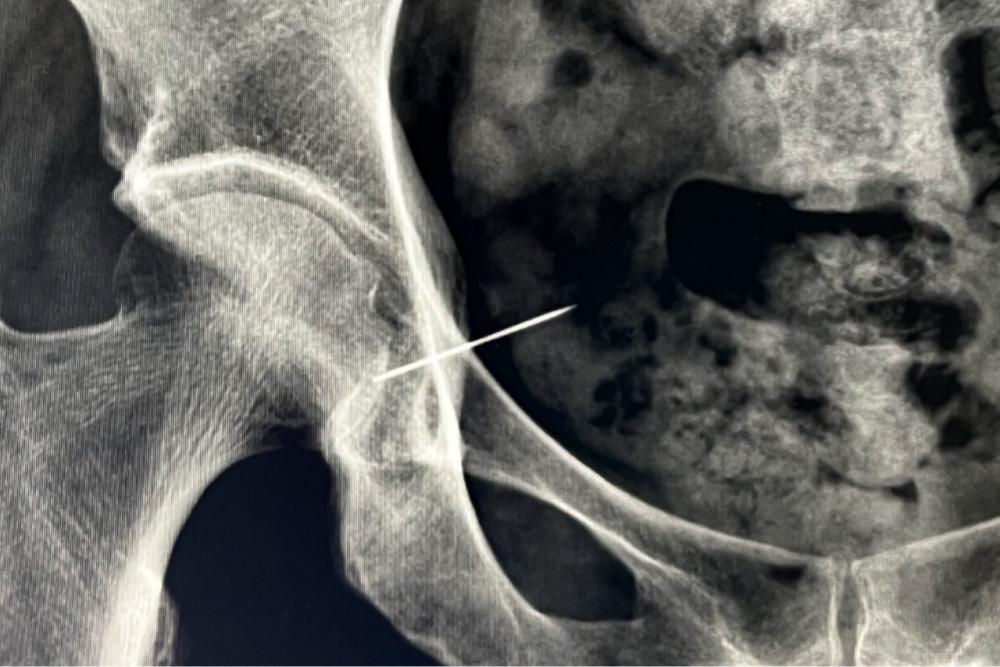

馬醫(yī)生仔細(xì)詢問了病史,黃阿姨說自己最近沒有受過外傷,也沒有局部注射、異物刺入等情況,那這是什么呢?經(jīng)過超聲檢查,考慮黃阿姨皮下有異物。憑借多年豐富的臨床經(jīng)驗(yàn),皮膚科團(tuán)隊(duì)初步判斷異物可能為縫衣針,X線檢查提示:示右側(cè)髖臼處金屬異物。原來,困擾黃阿姨許久的居然是一枚“腚”海神針......

為保險(xiǎn)起見,馬醫(yī)生通過放射檢查進(jìn)行核實(shí),X片上清晰地看到了針孔部位呈現(xiàn)斷裂狀態(tài),此刻,她懸著的心放下了。